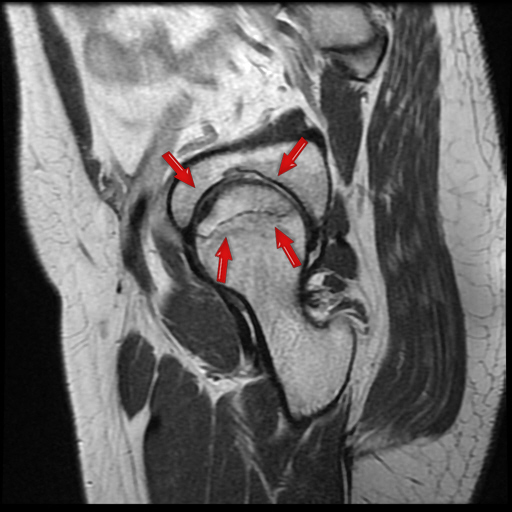

Avascular necrosis of the Hip Joint

Avascualar area of the top most portion of the ball of hip joint